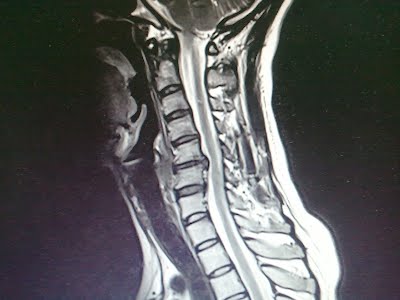

목디스크란 목뼈 사이에 있는 디스크가 손상되어 신경을 압박하는 질환을 의미합니다. 디스크는 젤리와 같은 수핵과 섬유륜으로 구성되어 있습니다. 섬유륜이 손상되면 수핵이 밖으로 밀려나와 신경을 압박하게 됩니다.

그렇다면 구체적인 목디스크 증상에는 어떠한 것들이 있는지 본문에서 자세히 알아보겠습니다.

목디스크 증상

목디스크 증상은 다양하지만, 가장 대표적인 증상은 목의 통입니다. 그 외 자세한 증상은 다음과 같습니다.